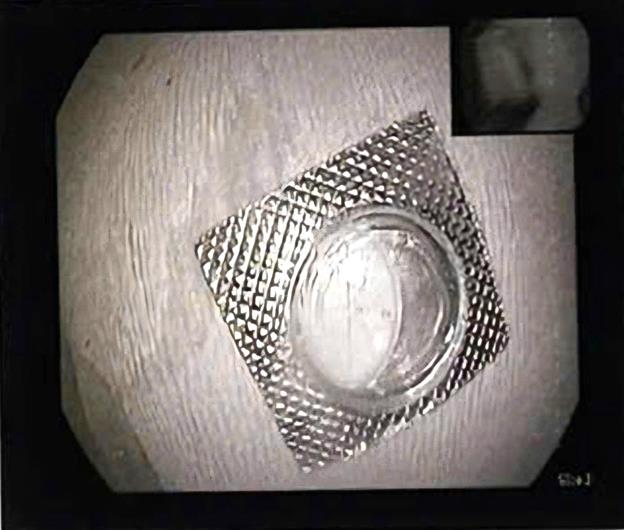

Vỏ thuốc có các cạnh sắc nhọn được bác sĩ lấy ra khỏi thực quản bệnh nhân.

Kết quả nội soi cho thấy, trong 1/3 giữa thực quản của bệnh nhân có một viên thuốc còn nguyên vỏ, kích thước 1,5x1,5 cm, với các góc sắc nhọn đã găm vào thành thực quản, gây phù nề, trầy xước và rỉ máu. Bác sĩ sau đó đã nhanh chóng sử dụng các dụng cụ chuyên biệt như kìm gắp dị vật và CAP (mũ chụp gắn đầu ống soi) để gắp dị vật ra ngoài một cách an toàn. Sau khi được gắp dị vật, bệnh nhân giảm đau rõ rệt và cảm thấy thoải mái hơn.